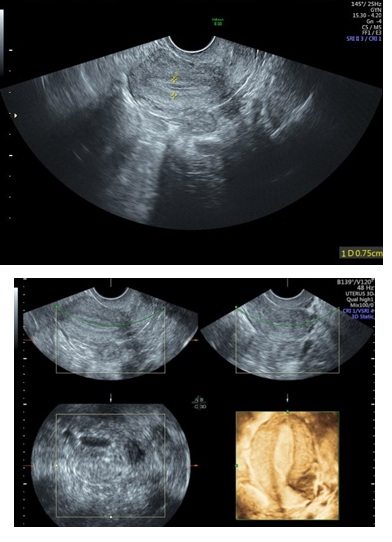

Figure 5: 2D & 3D USG showing Polyp in Uterine Cavity.

Three-Dimensional Ultrasonography (3D USG) in comparison to hysteroscopy is less invasive, cheaper, easily accepted by most patients and does not require much training. In most cases an endometrial polyp can be differentiated from the submucous fibroid based on the imaging characteristics. The polyps are typically round in shape, smooth in outline, and are generally echogenic, compared to the endometrium or are isoechoic to it. The underlying endometrial-myometrial interface is preserved (Figure 5). Moreover the presence of a vascular pedicle has a positive predictive value of up to 81.3%. Fibroids are more inhomogeneous, hypoechoic, and there is a loss of endometrial-myometrial interface. The percentage of the intra cavitary portions of the submucous fibroids i.e., grade of submucous myoma can be assessed on 3D USG by the degree of distortion caused by it (Picture 6).